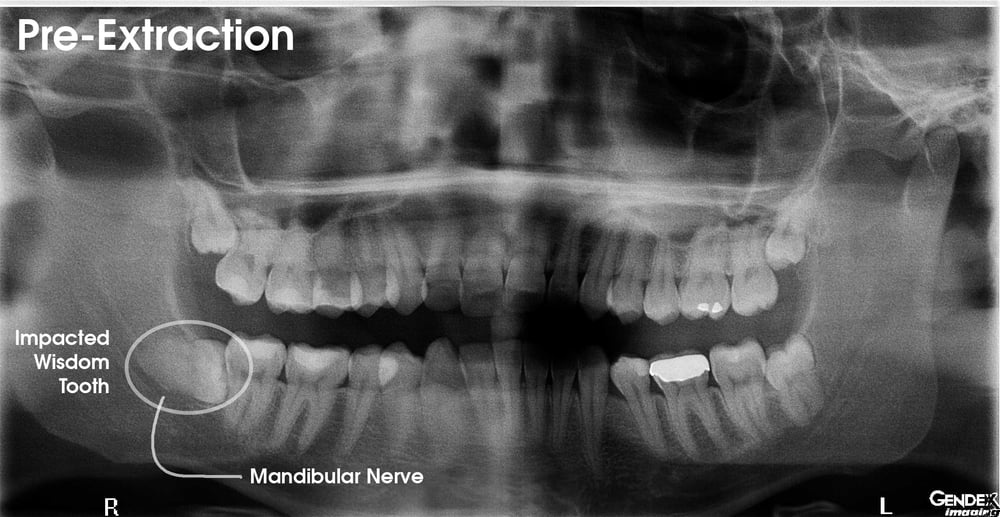

Impacted Wisdom Teeth Panoramic X Ray - TeethWalls

teethwalls.blogspot.comimpacted extraction prior

teethwalls.blogspot.comimpacted extraction prior

www.medicalnewstoday.comImpacted tooth xray image 1b. Impacted wisdom tooth x-ray pt2 by hotheadsquirrel5 on deviantart. Impacted extraction prior

www.medicalnewstoday.comImpacted tooth xray image 1b. Impacted wisdom tooth x-ray pt2 by hotheadsquirrel5 on deviantart. Impacted extraction prior